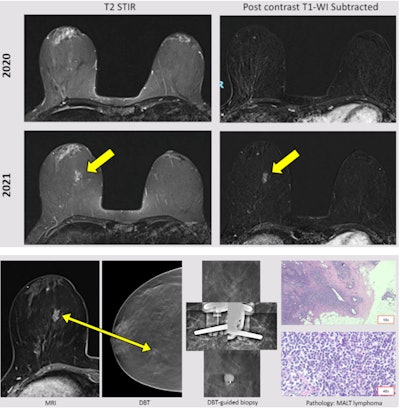

A 48-year-old woman diagnosed with Hodgkin lymphoma in 1999 and treated with chemotherapy and radiotherapy. Ultrasound was normal. MRI follow-up showed a new nonmass enhancement in the right breast (yellow arrow). DBT showed a focal asymmetry. Good correlation with the MRI finding. A DBT-guided vacuum-assisted biopsy was performed, leading to a diagnosis of mucosa associated lymphoid tissue (MALT) lymphoma.